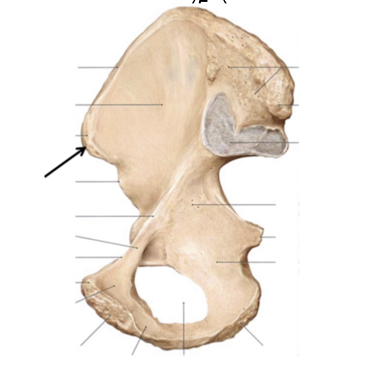

Wat is de naam van het aangeduide onderdeel?

Acromion